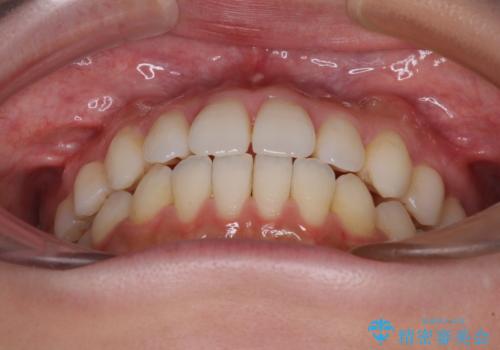

インビザラインで口を閉じやすく

- 下唇に上の前歯が当たることを気にして来院された患者様です。

上顎の親知らずを抜去し、歯列全体を後方に移動させるとともに、IPR(歯と歯の間を削る)を行うことで口元の閉じにくさを改善していくこととしました。

咬合力が強く、マウスピースを介した咬み込みが顕著であったため、奥歯の咬みにくさやIPRのスペースが改善しにくく、治療期間が思った以上にかかってしまいました。